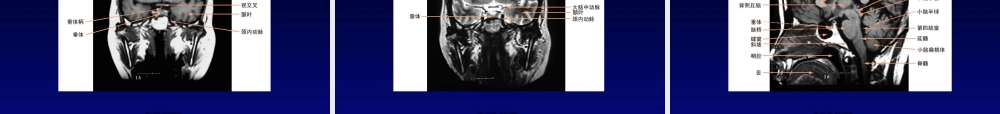

中枢神经系统影像学〔一〕中枢神经系统影像学〔一〕长安新安医院放射科李士光第一页,共九十五页。第一节检查技术第一节检查技术第二页,共九十五页。检查技术检查技术普通X线摄影数字减影血管造影计算机体层摄影磁共振成像技术第三页,共九十五页。检查技术普通X线摄影检查技术普通X线摄影头颅平片简单、经济第四页,共九十五页。检查技术普通X线摄影检查技术普通X线摄影常规摄影位置头颅侧位头颅正位第五页,共九十五页。检查技术数字减影血管造影检查技术数字减影血管造影动脉期动脉期颈内动脉造影(20°正位)颈内动脉造影(侧位)第六页,共九十五页。检查技术数字减影血管造影检查技术数字减影血管造影动脉期动脉期椎动脉造影(20°正位)椎动脉造影〔侧位〕第七页,共九十五页。检查技术计算机体层成像检查技术计算机体层成像常用CT检查方法又称平扫,为非增强扫描第八页,共九十五页。检查技术磁共振成像技术检查技术磁共振成像技术概述MRI的优点:对人体无电离辐射损伤、平第九页,共九十五页。检查技术磁共振成像技术检查技术磁共振成像技术MR图像特点数字化图像多参数成像多方位成像流动效应第十页,共九十五页。检查技术磁共振成像技术检查技术磁共振成像技术常用脉冲序列自旋回波〔SE〕:用于获取T1WI快速自旋回波〔FSE〕:用于获取T2WI和PDWI梯度回波〔GRE〕:主要用于获取T1WI和T2*WI,2D和3DMRA成像等反转恢复〔IR〕:主要用于脂肪抑制液体衰减反转恢复〔FLAIR〕:是IR序列的一种特殊类型,主要用于抑制脑脊液信号而使T2高信号病变显示得更清楚第十一页,共九十五页。MRI检查方法根本检查方法:检检查技术磁共振成像技术检查技术磁共振成像技术第十二页,共九十五页。第二节正常影像解剖第二节正常影像解剖第十三页,共九十五页。正常表现CT断层正常表现CT断层第十四页,共九十五页。正常表现CT断层正常表现CT断层第十五页,共九十五页。正常表现CT断层正常表现CT断层第十六页,共九十五页。正常表现CT断层正常表现CT断层第十七页,共九十五页。正常表现CT断层正常表现CT断层第十八页,共九十五页。正常表现CT断层正常表现CT断层第十九页,共九十五页。正常表现MR断层正常表现MR断层第二十页,共九十五页。正常表现MR断层正常表现MR断层第二十一页,共九十五页。正常表现MR断层正常表现MR断层第二十二页,共九十五页。正常表现MR断层正常表现MR断层第二十三页,共九十五页。正常表现脊...